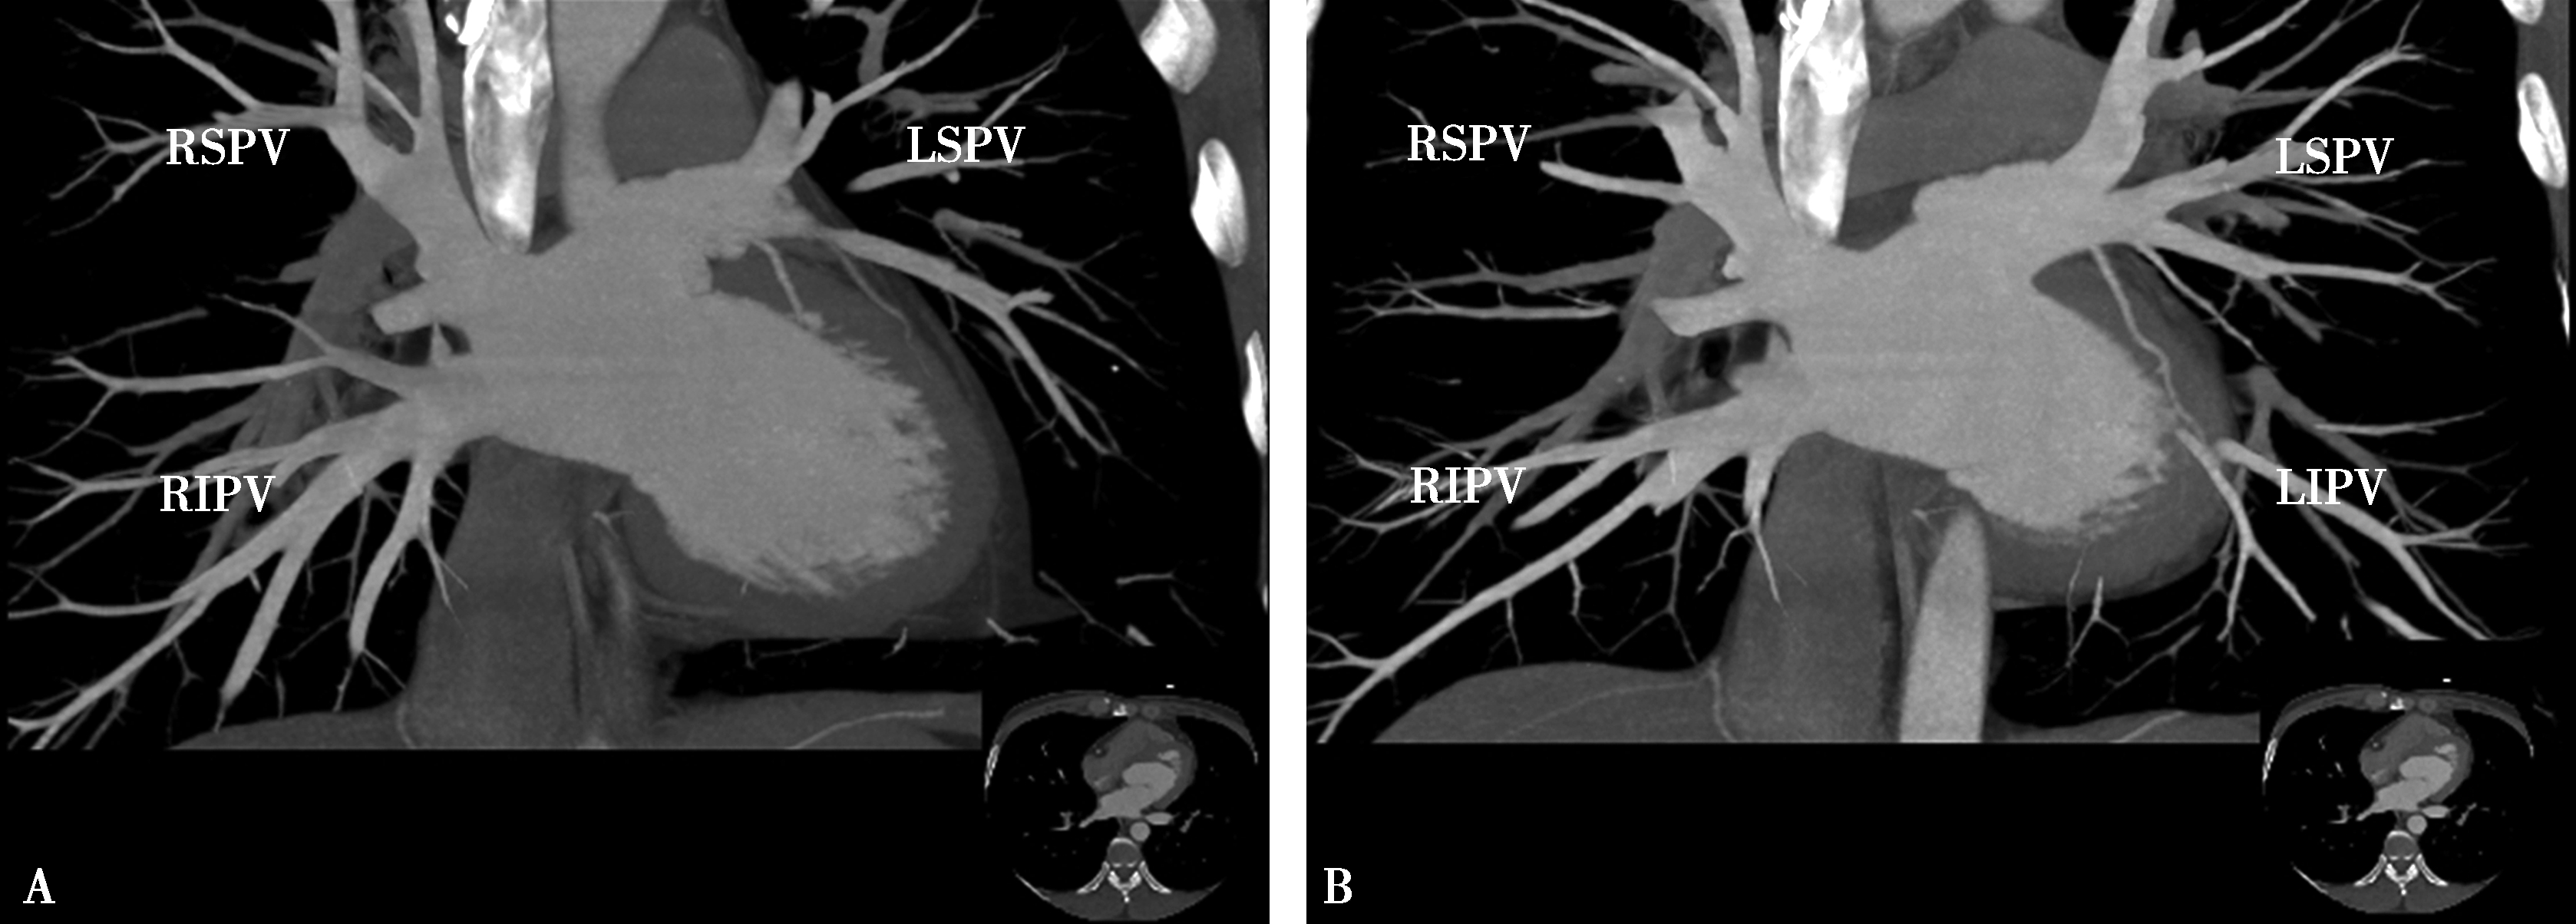

5.一期扫描 当ROI的CT值达到阈值时启动增强扫描程序。第一期扫描得到完整的肺静脉-左心房图像。如果达到诊断目的,可结束扫描(图8-1-11)。

图8-1-11 肺静脉CTA检查

A.上肺静脉(↑);B.下肺静脉(↑);C.肺静脉最大密度投影。LSPV:左上肺静脉;LIPV:左下肺静脉;RSPV:右上肺静脉;RIPV:右下肺静脉